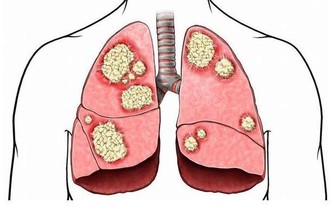

有人生氣最後導致了癌症……

生氣也會引發疾病,情緒也是影響健康的很大因素。